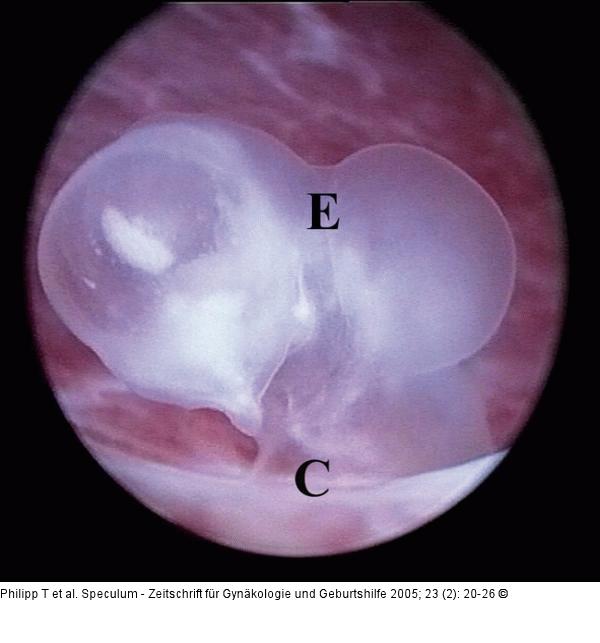

Abbildung 4: GD2-Embryo GD2-Embryo mit einer SSL von 3 mm. Eine Unterscheidung von kranialem und kaudalem Embryonalpol ist nicht möglich. Der Embryo (E) ist direkt an der Chorionplatte (C) adhaerent. Ein offenbar normaler Karyotyp (46,XY) wurde zytogenetisch diagnostiziert. |

GD2-Embryo mit einer SSL von 3 mm. Eine Unterscheidung von kranialem und kaudalem Embryonalpol ist nicht möglich. Der Embryo (E) ist direkt an der Chorionplatte (C) adhaerent. Ein offenbar normaler Karyotyp (46,XY) wurde zytogenetisch diagnostiziert. |